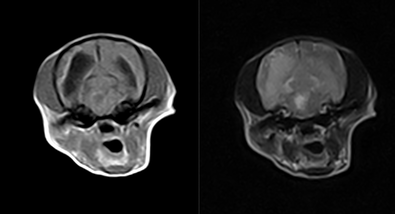

脳出血(硬膜下出血)CT

基礎疾患に皮膚腫瘤・DICあり

急性発症で即日検査実施

脳出血(硬膜下出血)MRI

上記症例と同一